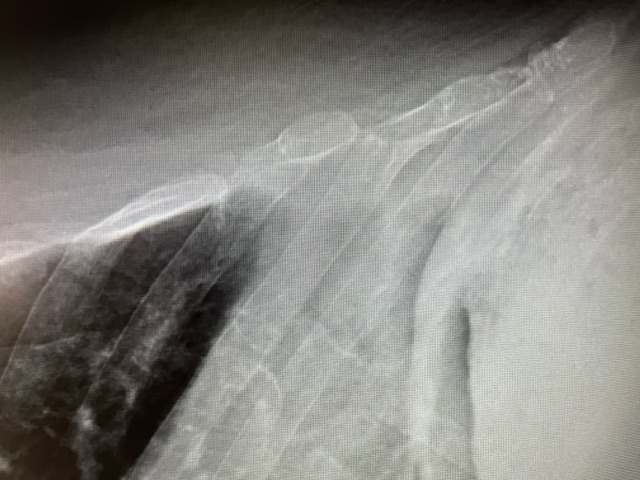

En la exploración física, presenta una saturación basal de 97% sin taquipnea asociada ni uso de musculatura accesoria con una auscultación pulmonar de crepitantes en base izquierda sin otros hallazgos. Ante lo anterior, decidimos solicitar una radiografía de parrilla costal y realizar una ecografía pulmonar en el centro de salud para descartar fractura asociada o neumotórax.

Se evidencia en la ecografía pulmonar sobre el 7º y 8º arco costal izquierdo una posible línea de fractura con falta de contigüidad en los rebordes costales sin evidenciar signos de neumotórax.

Posteriormente, se solicitó una radiografía de parrilla costal de carácter urgente que confirmó dichos hallazgos.

Por lo tanto, se trata de un caso de una fractura costal de 7-8º arco costal izquierdo tras caída casual.